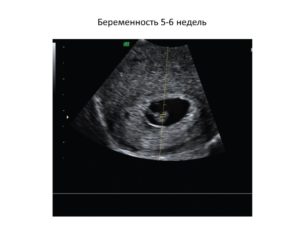

На фото: УЗИ плода в начале и в конце 6 недели беременности. На первом изображении определяется плодное яйцо без признаков эмбриона, а на втором, выполненном в конце 6 недели, эмбрион уже виден

При проведении УЗИ нормальной маточной беременности, в эндометриальном слое видно плодное яйцо, определяющееся как гипоэхогенное образование овоидной формы, размер длинной стороны которого составляет 1,0–1,3 см.

Правильная форма яйца, является одним из показателей нормального развития плода.

Копчико-теменной размер (КТР) плода (наибольшая длина), на данном сроке, составляет 4–6 мм, размер желточного мешка, также около 4–5 мм.

Наличие желточного мешка, считается одним из определяющих показателей, позволяющих исключить целый ряд патологий.

На сканограмме, в зависимости от положения занимаемого в матке, желточный мешок определяется либо в виде двух параллельных линий (боковая проекция), либо в виде замкнутого кольца (прямая проекция), плавающего в полости плодного яйца.

Разница между наибольшими величинами размера плодного яйца и эмбриона в норме должна равняться 5 мм. Немаловажным фактором, подтверждающим наличие беременности, является определение сердцебиения плода. До 6 недель частота сердечных сокращений (ЧСС) должна находиться в пределах 100–110 ударов в минуту, после 6 недель ЧСС возрастает до 120–125 и продолжает увеличиваться до 9 недель.

На УЗ-снимке: эмбрион на 6 неделе гестации. 1– контур тела матки, 2 – плодный пузырь (хориональная оболочка), 3 – желтое тело, 4 – эмбрион (отчетливо видна начальная стадия дифференциации амниотической оболочки)